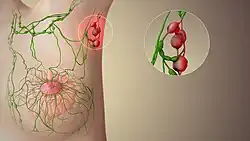

Lymph node enlargement or swelling is known as lymphadenopathy.[30] Swelling may be due to many causes, including infections, tumors, autoimmune disease, drug reactions, diseases such as amyloidosis and sarcoidosis, or because of lymphoma or leukemia.[31][30] Depending on the cause, swelling may be painful, particularly if the expansion is rapid and due to an infection or inflammation.[30] Lymph node enlargement may be localized to an area, which might suggest a local source of infection or a tumour in that area that has spread to the lymph node.[30] It may also be generalized, which might suggest infection, connective tissue or autoimmune disease, or a malignancy of blood cells such as a lymphoma or leukemia.[30] Rarely, depending on location, lymph node enlargement may cause problems such as difficulty breathing, or compression of a blood vessel (for example, superior vena cava obstruction[32]).

Enlarged lymph nodes might be felt as part of a medical examination, or found on medical imaging.[33] Features of the medical history may point to the cause, such as the speed of onset of swelling, pain, and other constitutional symptoms such as fevers or weight loss.[34] For example, a tumour of the breast may result in swelling of the lymph nodes under the arms[30] and weight loss and night sweats may suggest a malignancy such as lymphoma.[30]

In addition to a medical exam by a medical practitioner, medical tests may include blood tests and scans may be needed to further examine the cause.[30] A biopsy of a lymph node may also be needed.[30]

Cancer

Lymph nodes can be affected by both primary cancers of lymph tissue, and secondary cancers affecting other parts of the body. Primary cancers of lymph tissue are called lymphomas and include Hodgkin lymphoma and non-Hodgkin lymphoma.[35] Cancer of lymph nodes can cause a wide range of symptoms from painless long-term slowly growing swelling to sudden, rapid enlargement over days or weeks, with symptoms depending on the grade of the tumour.[35] Most lymphomas are tumours of B-cells.[35] Lymphoma is managed by haematologists and oncologists.

Local cancer in many parts of the body can cause lymph nodes to enlarge because of tumorous cells that have metastasised into the node.[36] Lymph node involvement is often a key part in the diagnosis and treatment of cancer, acting as "sentinels" of local disease, incorporated into TNM staging and other cancer staging systems. As part of the investigations or workup for cancer, lymph nodes may be imaged or even surgically removed. If removed, the lymph node will be stained and examined under a microscope by a pathologist to determine if there is evidence of cells that appear cancerous (i.e. have metastasized into the node). The staging of the cancer, and therefore the treatment approach and prognosis, is predicated on the presence of node metastases.

Lymphedema

Lymphedema is the condition of swelling (edema) of tissue relating to insufficient clearance by the lymphatic system.[37] It can be congenital as a result usually of undeveloped or absent lymph nodes, and is known as primary lymphedema. Lymphedema most commonly arises in the arms or legs, but can also occur in the chest wall, genitals, neck, and abdomen.[38] Secondary lymphedema usually results from the removal of lymph nodes during breast cancer surgery or from other damaging treatments such as radiation. It can also be caused by some parasitic infections. Affected tissues are at a great risk of infection. Management of lymphedema may include advice to lose weight, exercise, keep the affected limb moist, and compress the affected area.[37] Sometimes surgical management is also considered.[37]